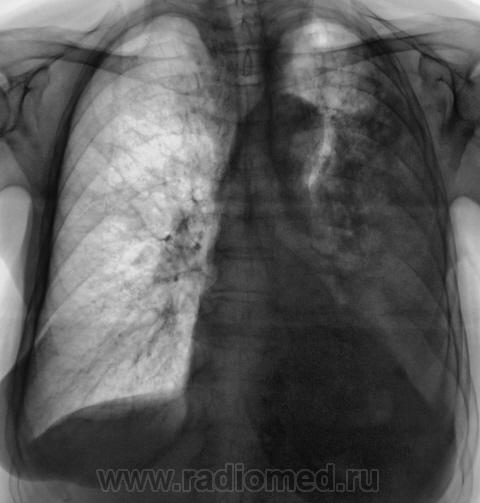

Контроль после флюорографии. Пациентка 3 года профилактическую флюорографию не проходила.

Подняли архив. Оказалось, что в 2008 г. пациентка лечилась в отделении по поводу пневмонии. После рентгенологического исследования "первичного", до лечения, настоятельно рентгенологом рекомендовалось провести рентген-контроль после лечения. Однако, на контроль пациентка направлена не была. Снимков нет, остались одни флюорограммы.